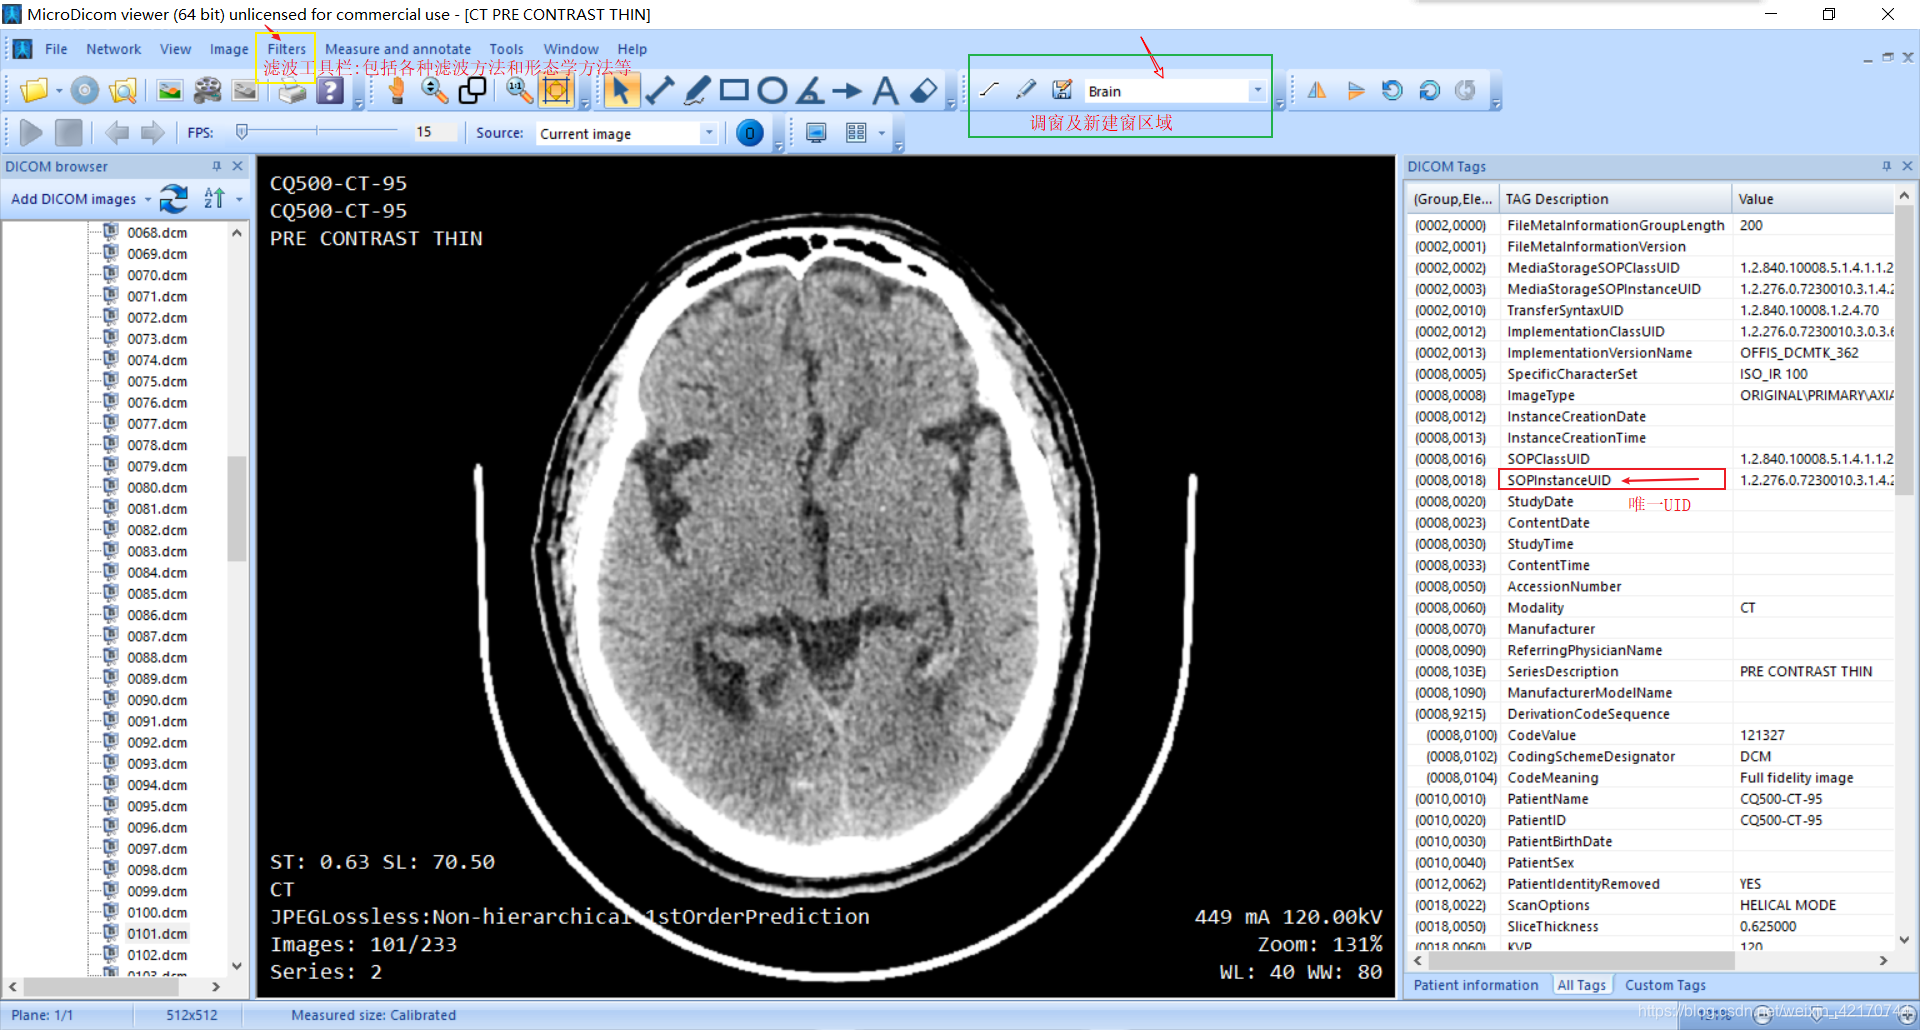

如上图标记所示,可用的也就是自适应调窗工具和滤波工具

右边All Tags可参考医学影像中Dicom的常用Tag分类与说明

上面的测距工具可能是针对于体素距离的,不适用于一般csv文件给的像素距离;但不知选择Plane Tool后怎么测距,即选择像素距离。

如上图标记所示,可用的也就是自适应调窗工具和滤波工具

右边All Tags可参考医学影像中Dicom的常用Tag分类与说明

上面的测距工具可能是针对于体素距离的,不适用于一般csv文件给的像素距离;但不知选择Plane Tool后怎么测距,即选择像素距离。